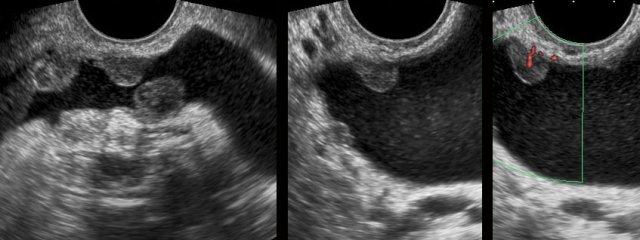

Ung thư bàng quang

Trong quá trình siêu âm đầu dò âm đạo thường quy, bác sĩ phụ khoa phát hiện một khối đặc, tăng sinh mạch máu rõ, bờ tương đối rõ với đường kính 2,5 cm, xuất phát từ thành bàng quang.

Bệnh nhân không có tiền sử đái máu hay rối loạn tiểu tiện.

Phẫu thuật nội soi bàng quang xác nhận ung thư biểu mô tế bào chuyển tiếp độ 1.